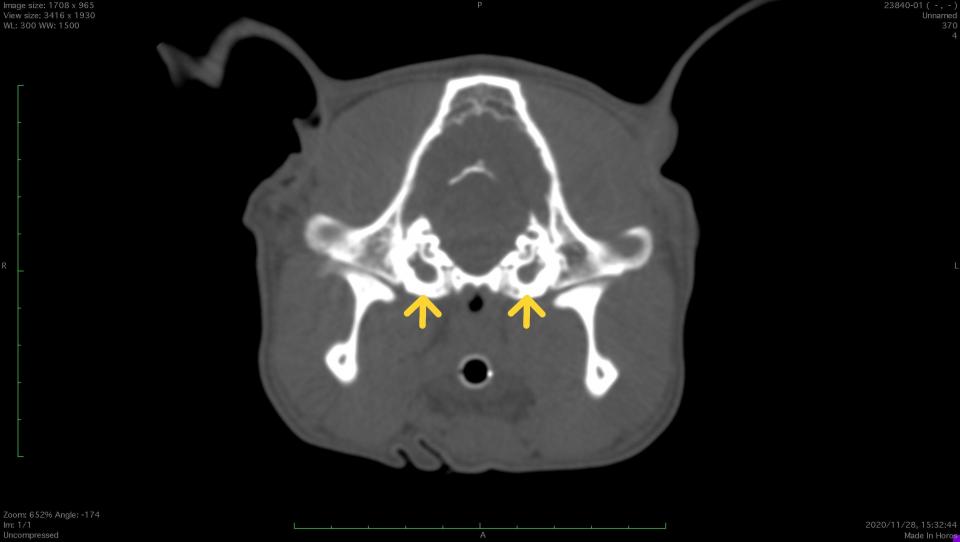

CT検査では、正常な鼓室胞は空気で満たされているので左画像のように黒く映ります。

一方、本症例では液体や軟部組織で鼓室胞内が満たされていることがわかります。